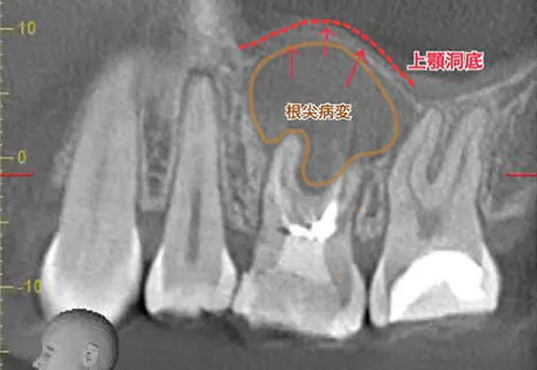

診断:CTによる精密検査で見つかった複雑な感染源

CTでしっかりと診断を行ったところ、とても深刻な状況でした。根管治療が重要ですが、それだけでは完全な治癒が望めない場合もあり、歯槽骨の再生を促す外科的処置が必要になることもあります。

こちらの患者様のように、歯槽骨のダメージが大きい症例では、根管内の感染と歯肉溝内の感染が両方の原因となっていることが多いですね。

根尖病変によりCT上で黒く写っていた部分が白っぽくなっているのがわかりますか?

溶けていた部分の歯槽骨が回復しているということです!

また、上顎洞の肥厚は収まり、頬側の歯槽骨もくっきり映っています。予想以上に歯槽骨が回復しているので、今後外科的処置をしなくても良いのではないかと判断しました。大きなダメージがあった歯なので補綴物を入れた後も欠かさずに経過観察を行い、少しでも長くご自身の歯で生活して頂きたいと思います。